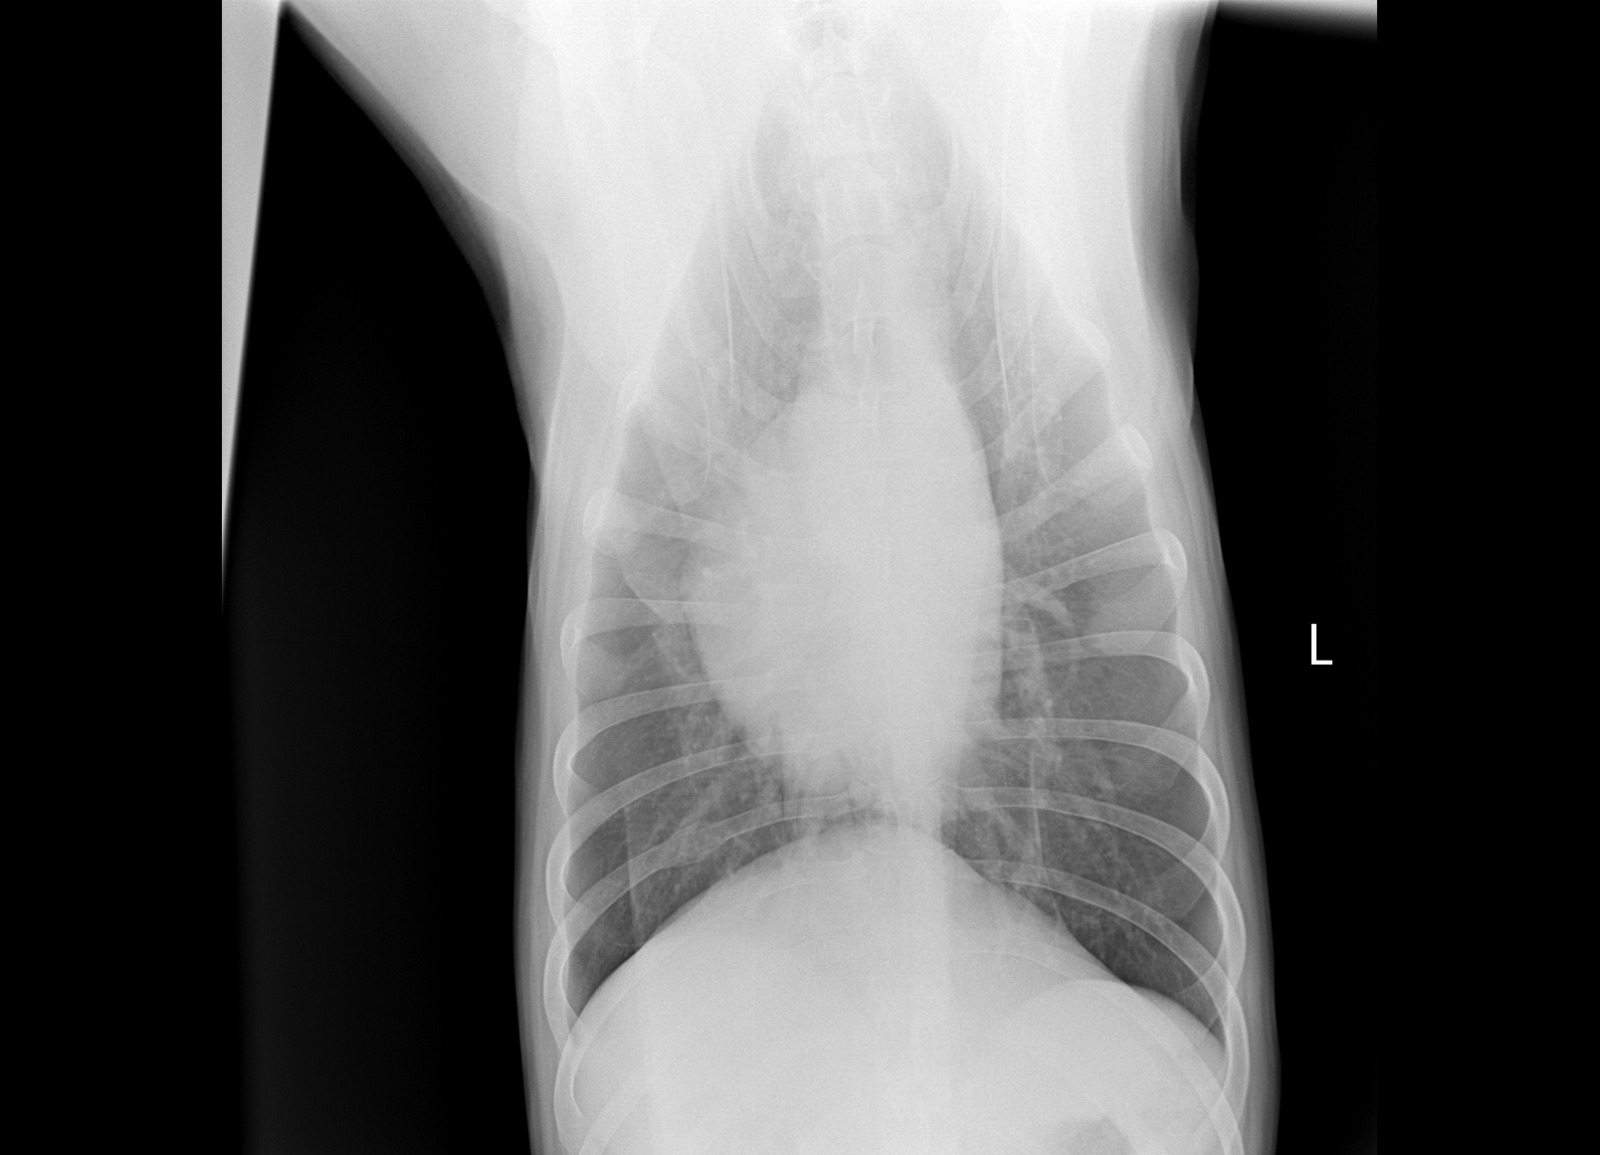

Рентген

Вложения

IMG-20241115-WA0049.jpg

IMG-20241115-WA0050.jpg

IMG-20241115-WA0052.jpg

IMG-20241115-WA0053.jpg

IMG-20241115-WA0051.jpg

Интересно, а изменения в бронхах на рентгене от диро или результат хронического бронхита?

Марта+ писал(а): 26 ноя 2024, 20:19 Интересно, а изменения в бронхах на рентгене от диро или результат хронического бронхита?

У Зевса кожная форма. Не от диро.